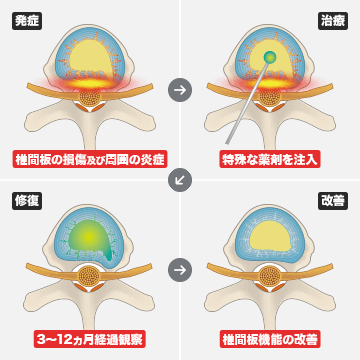

治療内容

損傷した椎間板に特殊な薬剤を入れ、椎間板機能の改善を目的とした治療方法です。特に変形したり、狭くなっている椎間板に対して治療を行っています。

-

- 効果

- 3~12ヵ月で症状の改善が期待できます。

-

- 副作用

- 治療後2週間程度は一時的に症状が悪化する可能性があります。また椎間板の容量が増えたことにより周りの筋肉や靭帯が広がることによって筋肉痛や腰の違和感が出現することがあります。